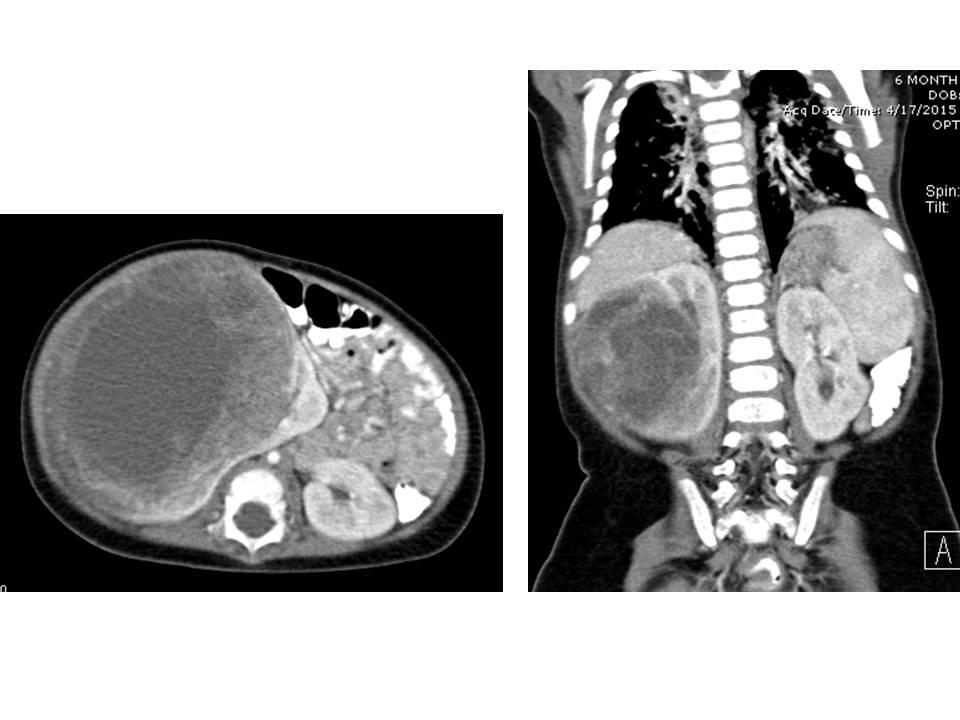

Airp Best Cases In Radiologic Pathologic Correlation Congenital Mesoblastic Nephroma Radiographics